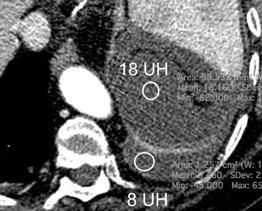

Hemorrágica………….30-70 UH

“Simpático”………….,,,,<15 UH

Urogénico……………….< 15 UH

Entérico.. ………………+/- 15UH

Biliar, Quiloso……………..<0 UH

Urinoma

Hemotórax

Quilotórax

Abramowitz1 Y et al. Pleural Effusion: Characterization with CT Attenuation Values and CT Appearance .AJR 2008